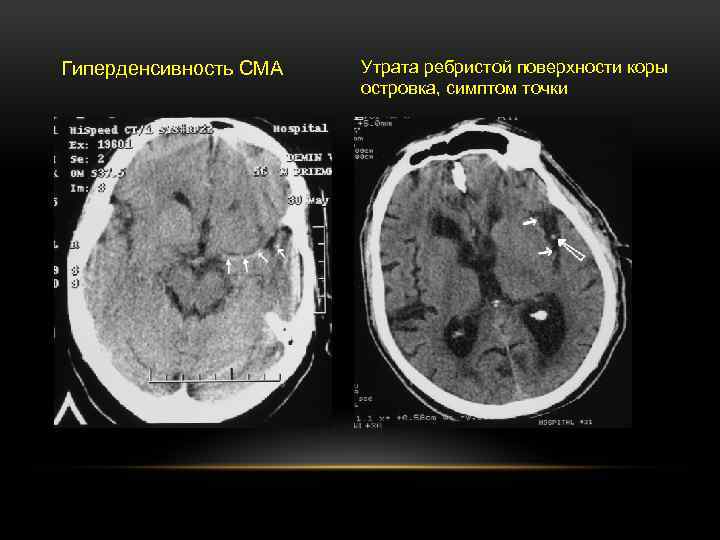

РАННИЕ КТ ПРИЗНАКИ ИШЕМИЧЕСКОГО ИНСУЛЬТА • • • гиподенсивность менее трети бассейна васкуляризации СМА + • утрата контраста серого и белого вещества мозга в области головки хвостатого ядра • утрата контраста серого и белого вещества мозга в области конвекситальной коры • • утрата ребристой поверхности коры островка + гиподенсивность более трети бассейна васкуляризации СМА + утрата контраста серого и белого вещества мозга в области лентикулярного ядра + сглаженность борозд менее трети бассейна васкуляризации СМА сглаженность борозд более трети бассейна васкуляризации СМА сдавление боковых желудочков мозга гиперденсивность ствола СМА «Симптом точки» + ранняя геморрагическая трансформация

Гиперденсивность СМА Утрата ребристой поверхности коры островка, симптом точки